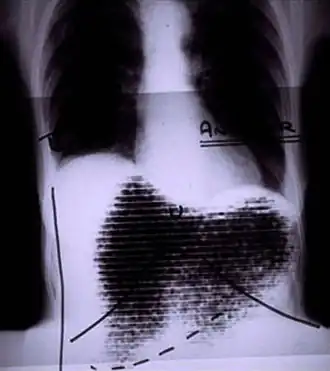

![]() Manual image fusion of x-rayed and rectilinear scanned chest | |

A rectilinear scanner is an imaging device, used to capture emission from radiopharmaceuticals in nuclear medicine. The image is created by physically moving a radiation detector over the surface of a radioactive patient. It has become obsolete in medical imaging, largely replaced by the gamma camera since the late 1960s.[1][2][3]